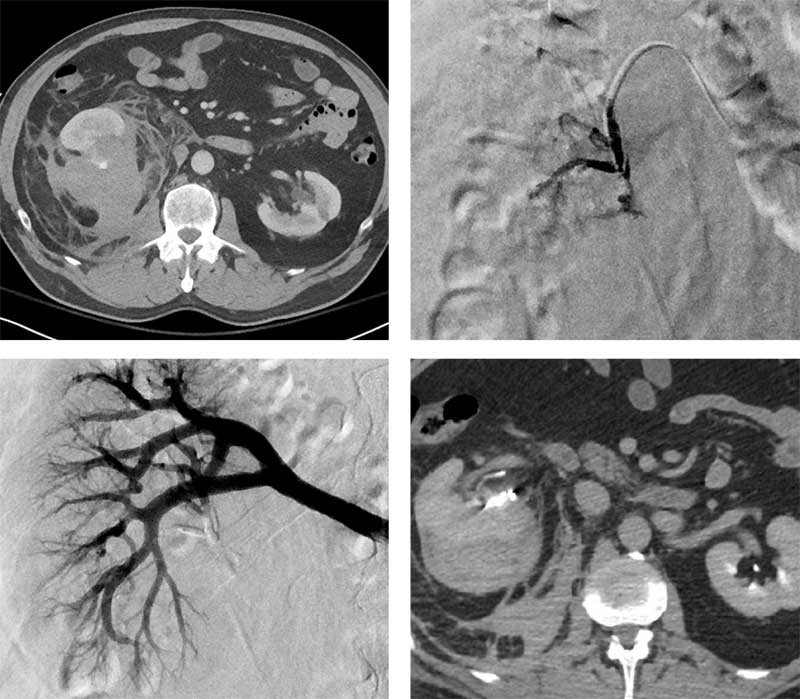

60-year-old male patient who developed right flank pain and hematuria after falling. He became hypotensive and had a syncopal event. CT showed a large right retroperitoneal hematoma and a grade III renal laceration with evidence for active extravasation. He was transferred to our hospital where he became hypotensive with SBP in the 60s. He was transfused with 2u PRBC and referred for angiography and embolization.

Arterial access was gained via the right common femoral artery. A Sos-2 catheter was used to catheterize the right renal artery. Selective angiography demonstrated a pseudoaneurysm arising from the lower pole branch of the main renal artery. A Renegade™ HI-FLO™ Microcatheter was advanced into this vessel, and 0.2 mL of Obsidio Embolic was used for embolization. Follow-up angiography demonstrated successful occlusion of this vessel.

He had no additional signs of ongoing bleeding with a stable hgb/hct after embolization. No additional transfusions were required. Follow-up CT demonstrated no further contrast extravasation and some retraction of the perirenal and retroperitoneal hematoma. He was discharged home 5 days after embolization.